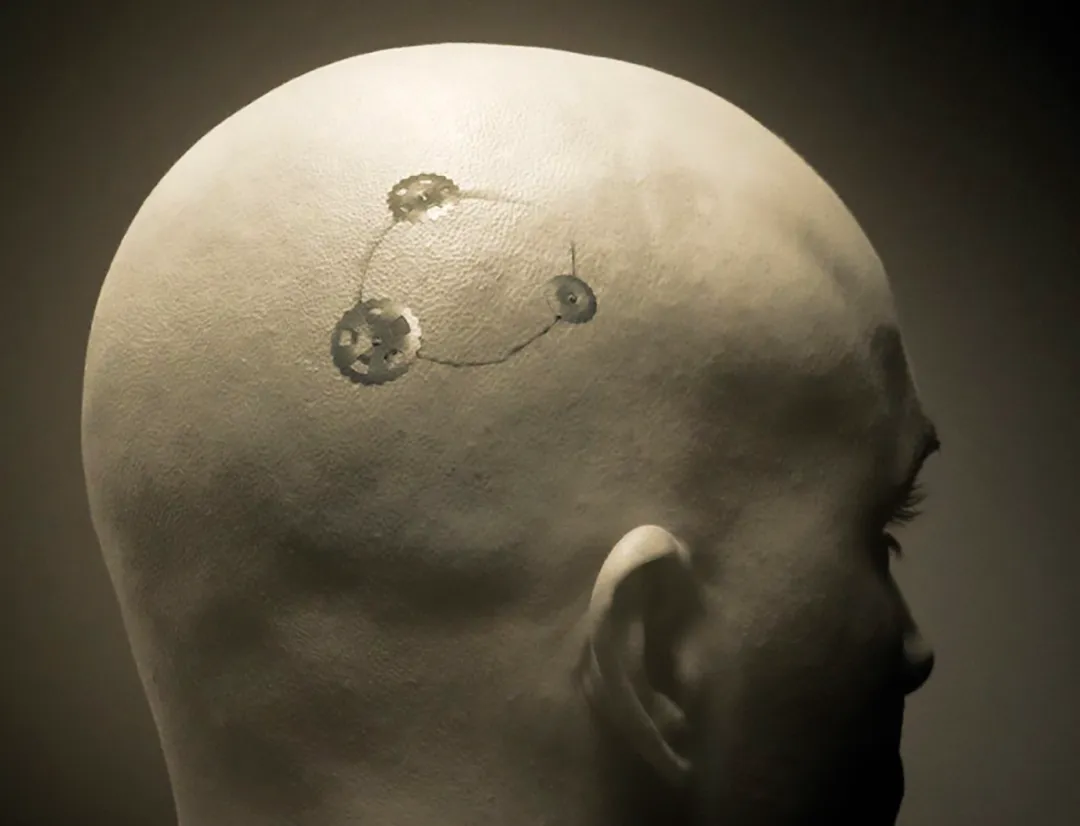

Craneoplastía

Contamos con un amplio portafolio para el área de craneoplastía, con soluciones...

Cierre Craneal

Con un perfil de placas y tornillos de 0.3 mm, el sistema de recubrimiento ThinFlap de...

Cierre de Trépanos

El sistema proporciona un enfoque simplificado para la fijación craneal, lo que reduce...